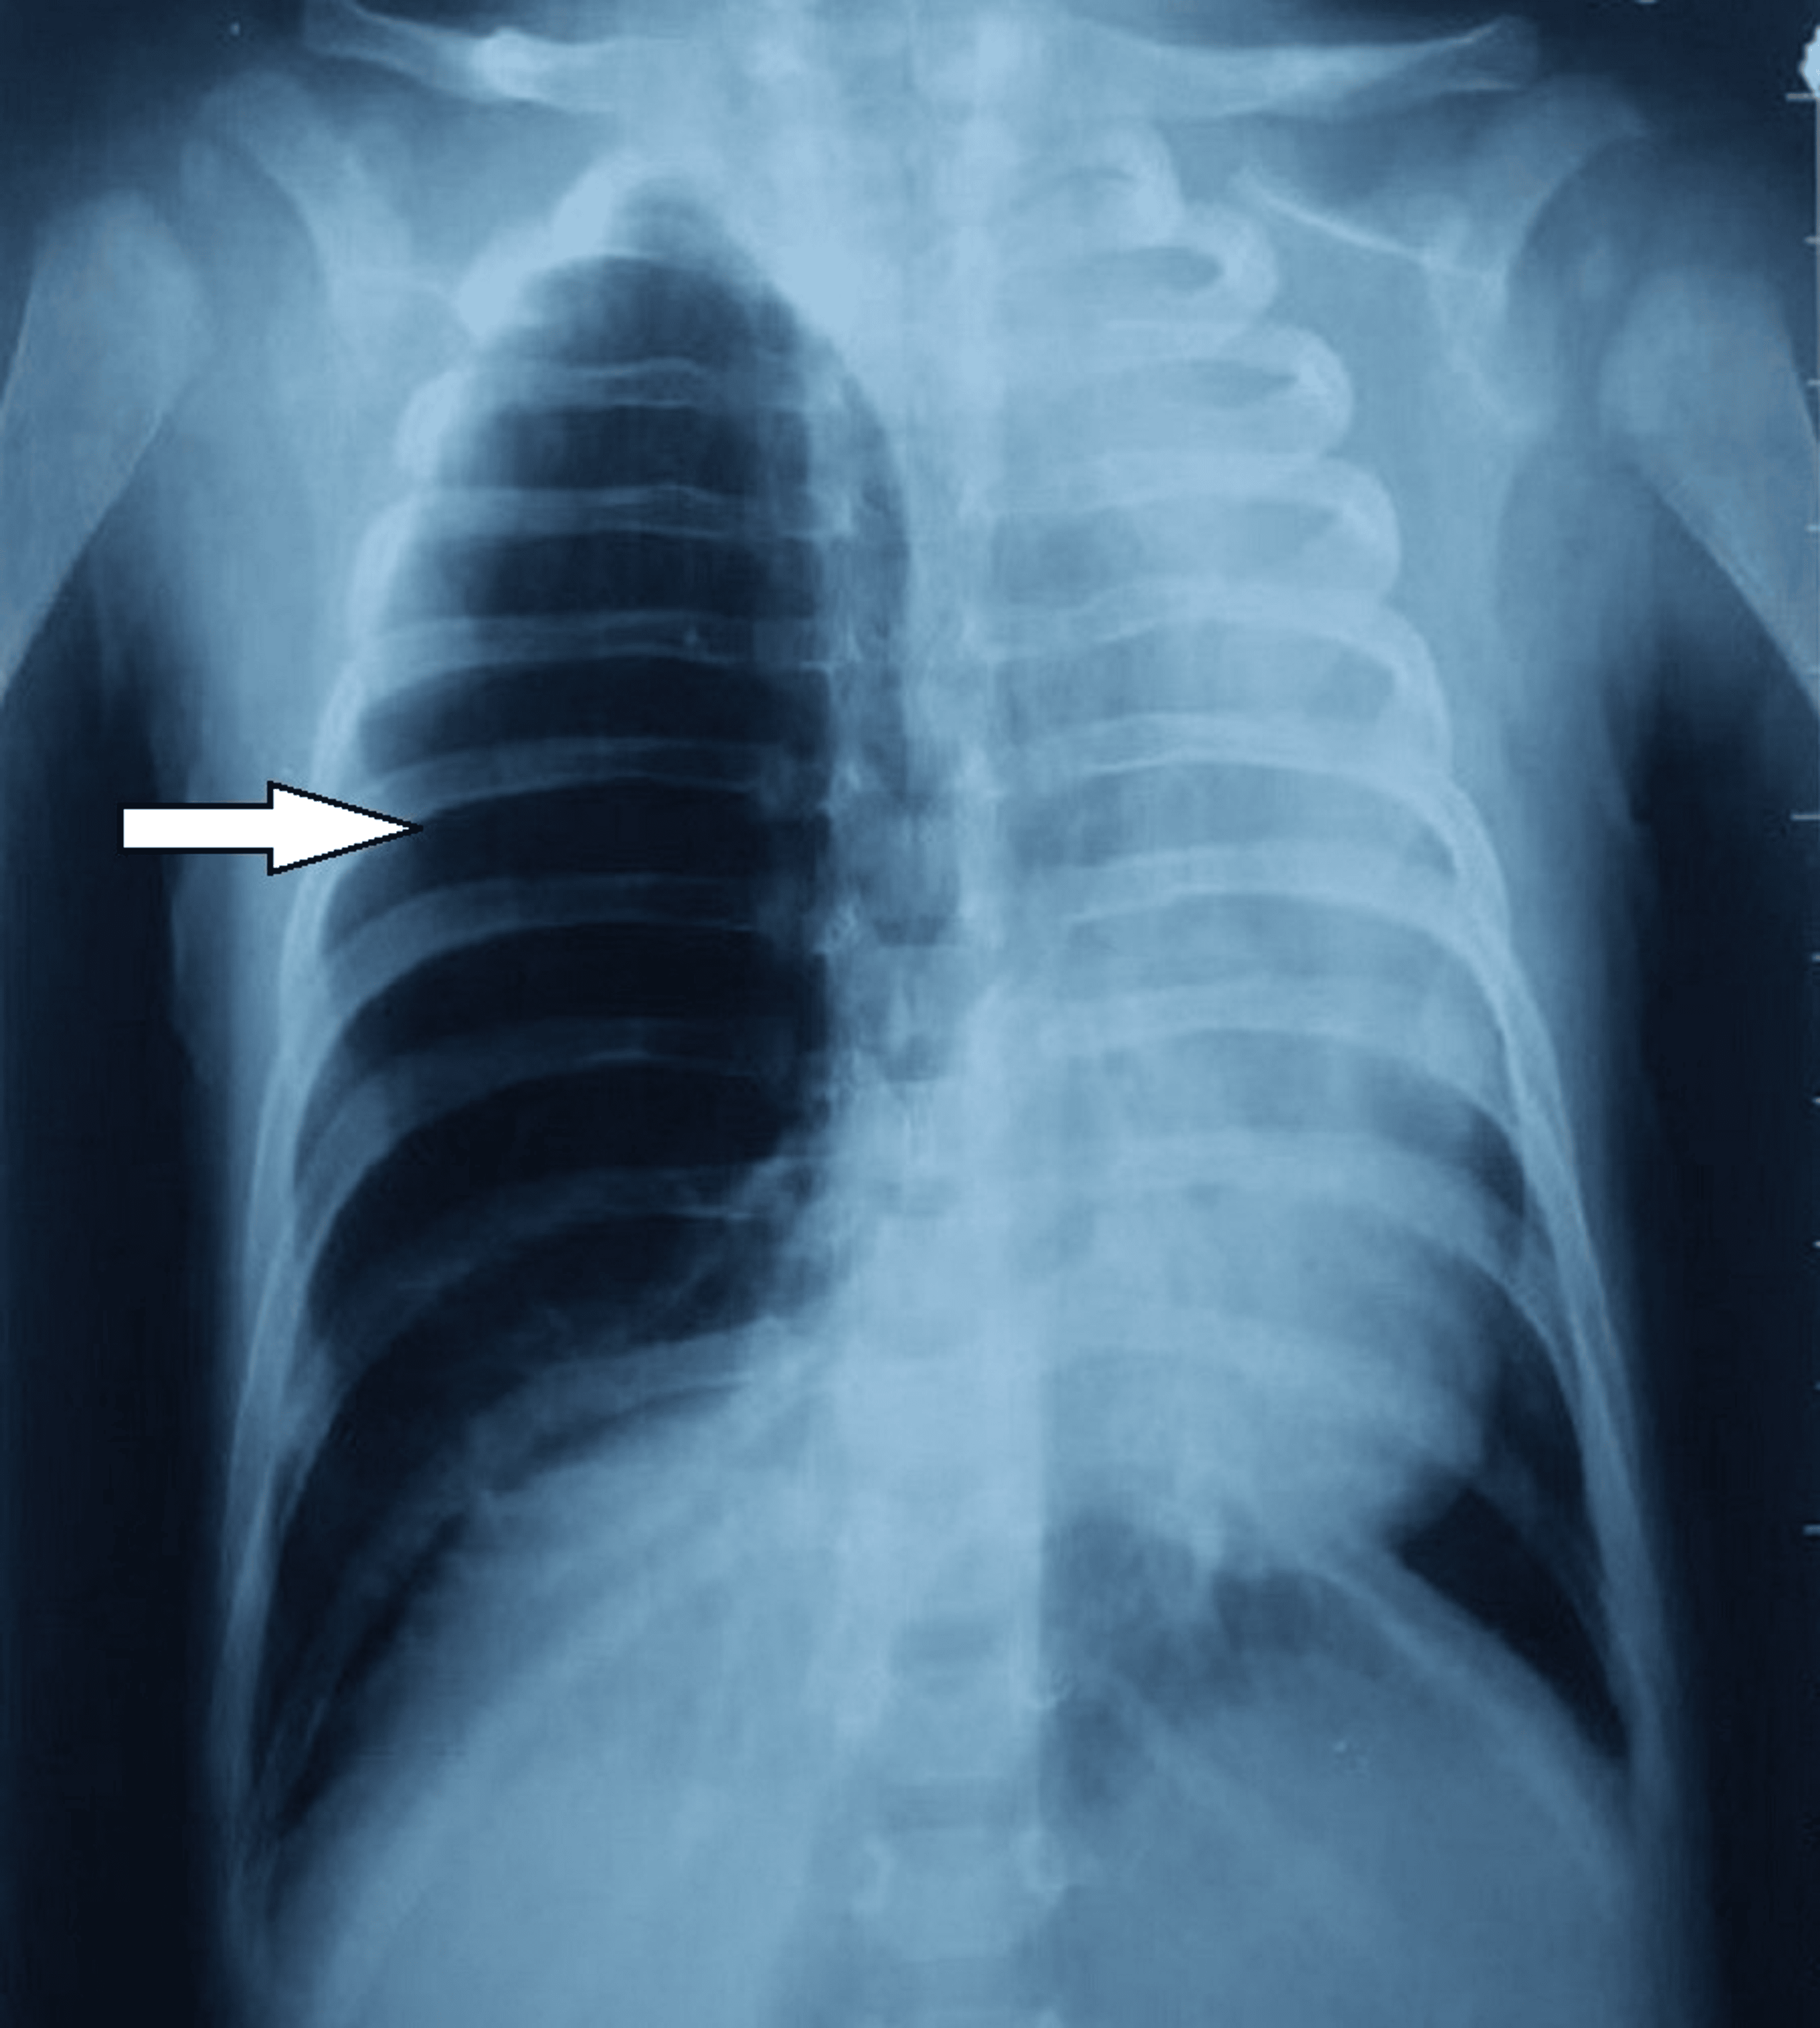

From www.researchgate.net

Chest Xray showing hyperinflation of the left upper lobe, with Congenital Lobar Emphysema Chest X Ray Radiolucent expanded right lung in a newborn, compatible with congenital lobar emphysema (rml & rul). the hrct findings were characteristic of congenital lobar emphysema (cle). congenital lobar emphysema (cle). congenital lobar emphysema is a rare lung malformation, with an estimated incidence of one case per 20. congenital lobar emphysema (cle), also known as congenital alveolar overdistension,. Congenital Lobar Emphysema Chest X Ray.

The xray showing congenital lobar emphysema LUL Download Scientific Congenital Lobar Emphysema Chest X Ray congenital lobar emphysema is a rare lung malformation, with an estimated incidence of one case per 20. congenital lobar emphysema (cle), also known as congenital alveolar overdistension, is a developmental. the hrct findings were characteristic of congenital lobar emphysema (cle). Radiolucent expanded right lung in a newborn, compatible with congenital lobar emphysema (rml & rul). congenital. Congenital Lobar Emphysema Chest X Ray.